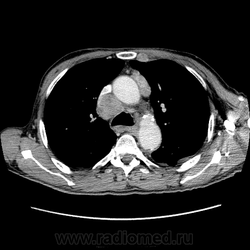

Печень. Процесс в средостении, бр.пол., забр.пр-ве. МСКТ.

Здравствуйте, коллеги! Мужчина около 70 лет. Жалобы: слабость, утомляемость около 3х месяцев, чувство тяжести на желудке после еды. Анамнез: онко не было. С вышеописанными жалобами обратился ко врачу, сделали ФГЭДС - признаки гастродуоденита, по биопсии - N. В течение 2х последних недель существенно похудел и начал желтеть. Выполнена МСКТ

+1. А вот образование средостения к чему отнести?

Вероятно метастазы

А как насчет холангиокарциномы с тромбозом воротной вены и мтс в средостение, лимфоузлы брюшной полости и забрюшинного пр-ва?

Я - за.

Внесу лепту: видел пару гистологически подтверждённых ХЦР в периферических отделах правой доли, естественно без расширения протоков, одна прорастала диафрагму и метастазировала в узлы ворот, вторая прорастала сегментарные сосуды, вызывая атрофию двух кажется сегментов. На мрт выглядели примерно одинаково: большой солидный периферический компонент, быстро интенсивно накапливающий контраст. На отсроченных томограммах - вымывание контраста из периферической части и накопление в центральной зоне распада. ГЦР вроде и гиповаскулярный бывает, самому не встречался правда.